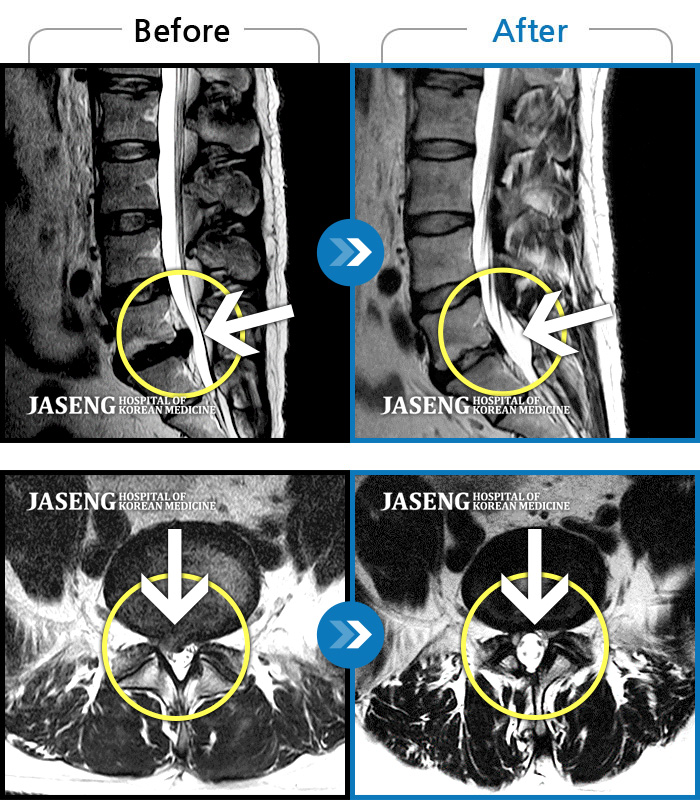

[뱸] 19.11.28~25.05.06

ȯںп Ǹ ǿ ԿǾ, ο ġ ۿ Ƿ ġḦ Ͻñ ٶϴ.